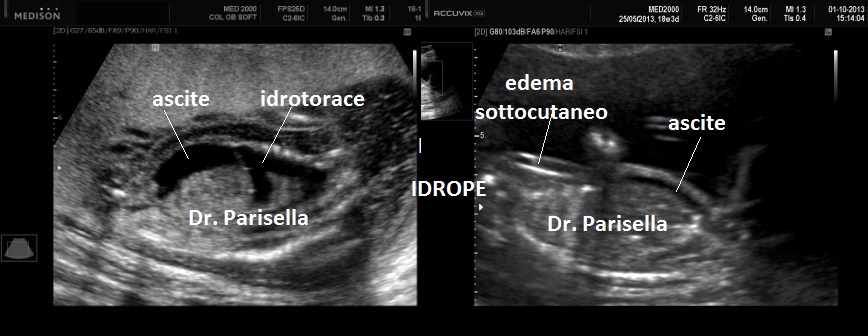

I segni ecografici sono:

• edema del sottocute: spessore > 5 mm.

• iperplacentosi: spessore placentare > 6 cm.

• polidramnios

• ascite

• effusione pericardica

• effusione pleurica

Come detto in precedenza l'accumulo di liquido deve interessare almeno due compartimenti.

Un primo orientamento sulle cause di idrope può essere fatto attraverso la localizzazione dell'accumulo di liquido: un accumulo generalizzato sin dal principio orienta verso una causa sistemica come l'anemia, mentre un accumulo inizialmente localizzato porta ad orientarsi verso una patologia locale ( es.: versamento pleurico >>>> Malformazione Adenomatoide Cistica Congenita del polmone).